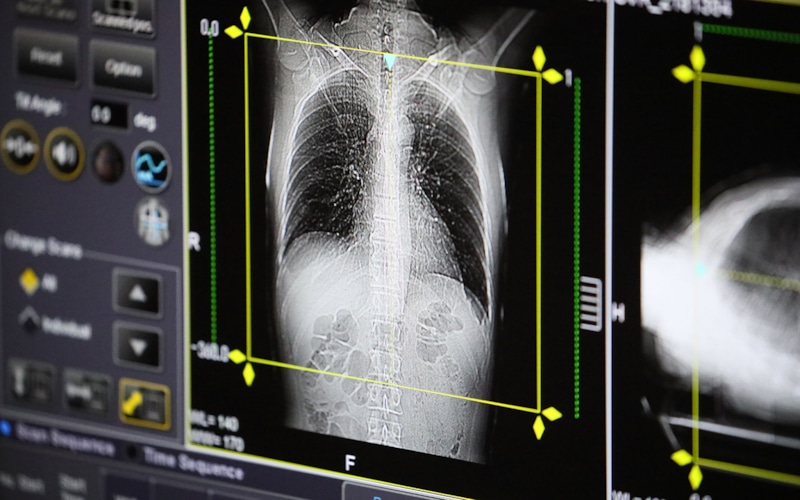

В России зафиксирована тенденция роста заболеваемости пневмонией, в том числе микоплазменной.

В Роспотребнадзоре сообщили о появлении групповых очагов инфекции в детских учреждениях. Основным возбудителем является микоплазма — бактерия, которая может длительно находиться в организме и активироваться при ослаблении иммунитета. В школах и детсадах усилены проверки на наличие признаков заболевания у детей, передает RTVI. Вспышки пневмонии отмечены уже в 16 регионах России, в числе пациентов и взрослые, и дети.